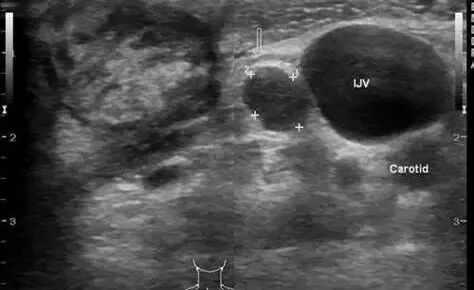

颈部有僵硬感,颈部转动各方向时的运动都受到限制,随着病情的发展,患者还会出现畸形,一般后凸畸形不明显,多为生理曲度变平。